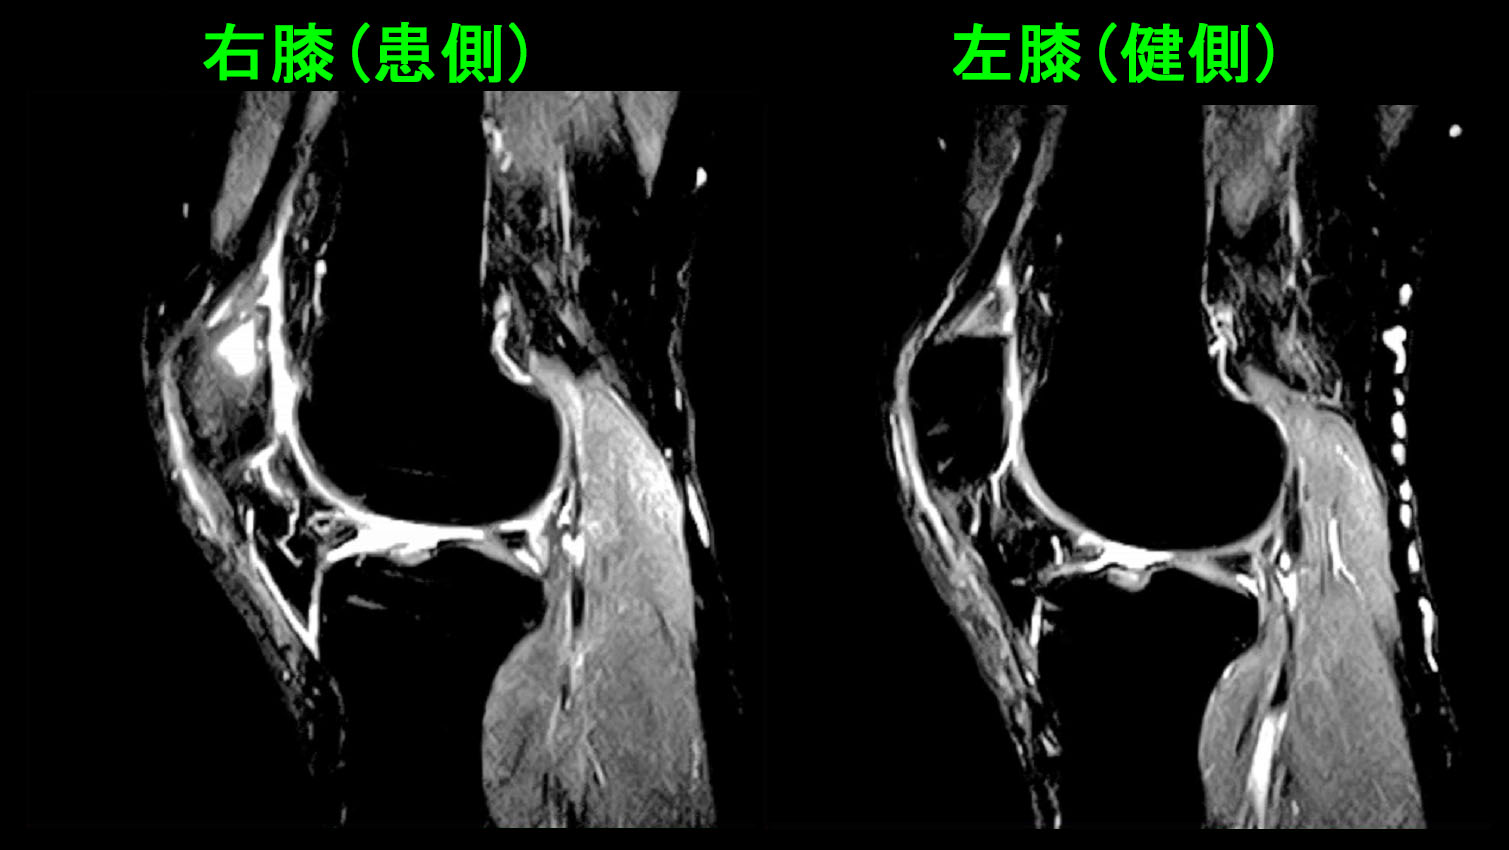

42才男 半年続く右膝痛MR.jpg

MRI検査(STIR条件)では右膝の膝蓋骨の上部が白くなっており、疲労骨折の所見でした。一度発生した疲労骨折の痛みは、発症原因の縄跳びを止めても、普通の日常生活だけでも改善しなかったのです。疲労骨折は運動部の中学生や高校生にみられる骨損傷で、運動を休めば普通は治っていきます。